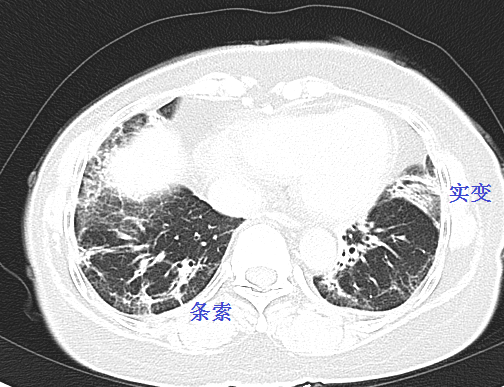

患者女性,59岁,间质性肺炎